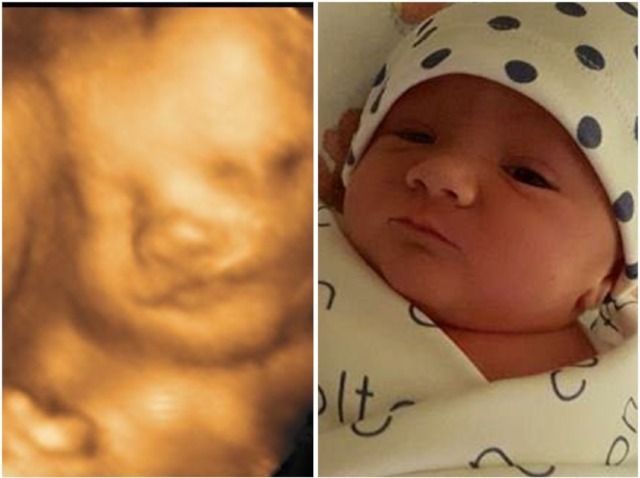

Our 4D/HD ultrasounds can begin as early as 7 weeks, giving you a clear and awe-inspiring first look at your baby. And it’s never too late—we’re experienced in scanning up to 42 weeks into pregnancy.

Every ultrasound—even 4D/HD—begins with a 2D scan, also known as grayscale. These are the classic black-and-white images you're used to seeing. This foundational imaging technique reveals a wealth of information, and we’re excited to share that with you.

Our 2D Connection session provides essential information and, most importantly, a beautiful opportunity to begin bonding with your baby. From there, you can personalize your experience by adding 4D/HD imaging and selecting from a variety of thoughtful extras to create the perfect package for you.